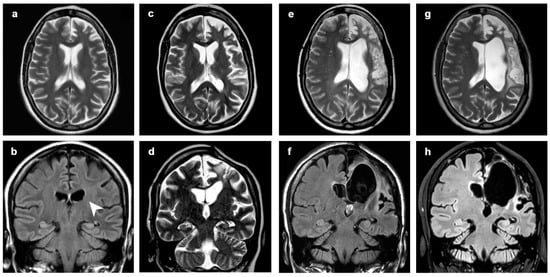

3.1. Atrophic Changes

3.2. Changes in Signal Intensity